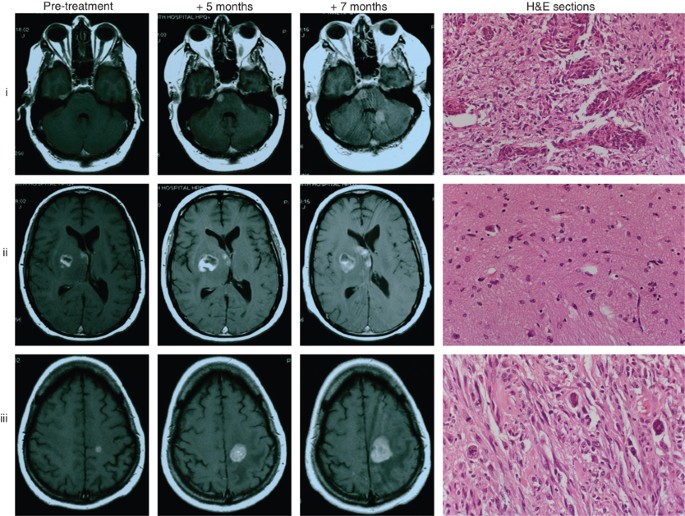

Imaging and histopathology

At post-mortem, three separate areas of the brain tumour were sampled, one area was from the central pons, one from the right basal ganglia and one from the left frontal region. The pontine lesion and right basal ganglia were part of the same tumour mass. Histopathological examination revealed that the pontine tumour was a glioblastoma (WHO grade IV), the right basal ganglia tumour was a fibrillary astrocytoma (WHO grade II) and the left frontal tumour was a gliosarcoma (WHO grade IV). Serial magnetic resonance imaging at diagnosis and during treatment and the corresponding H&E sections showed three regions of tumour: (i) glioblastoma, (ii) astrocytoma and (iii) gliosarcoma (Figure 1).